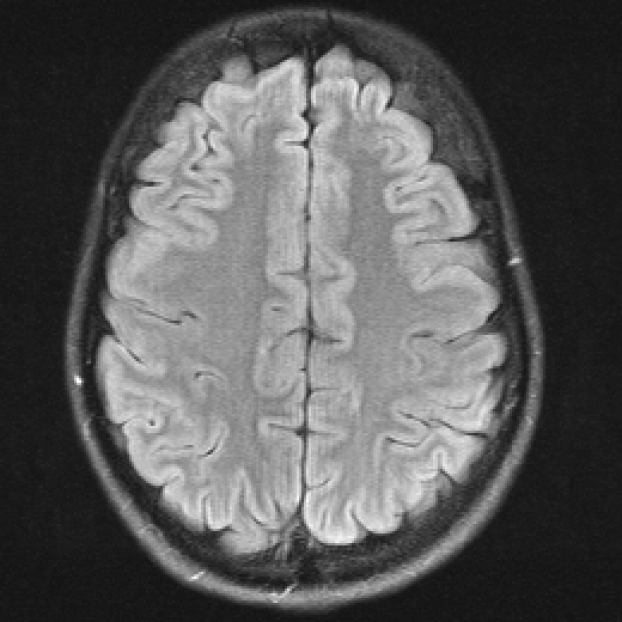

In Figure 1 we show a toy example of misjudgments that occur when evaluating the quality of a 2D MRI scan compared to degraded versions of the same image with the selected measures. PSNR even yields the same value for all the very different degradations, and all of the tested measures fail in the judgement of massive local information loss (d), as well as in the judgment of stochastic noise (e) versus block artefacts (f). This toy example served as an inspiration to study the behavior of the standard measures in real-life medical imaging tasks.

Figure 1: Illustrative toy example of problems occuring when using the standard FR-IQA measures PSNR/SSIM/LPIPS for the evaluation of medical images. Degradations have been added artificially to the reference (a) MRI scan: contrast enhancement (b), brightness change (c), hole (d), Gaussian White noise (e), jpeg compression (f). PSNR yields the same value for all degradations, SSIM and LPIPS fail to identify the hole (d), and misjudge the quality of (e) and (f).